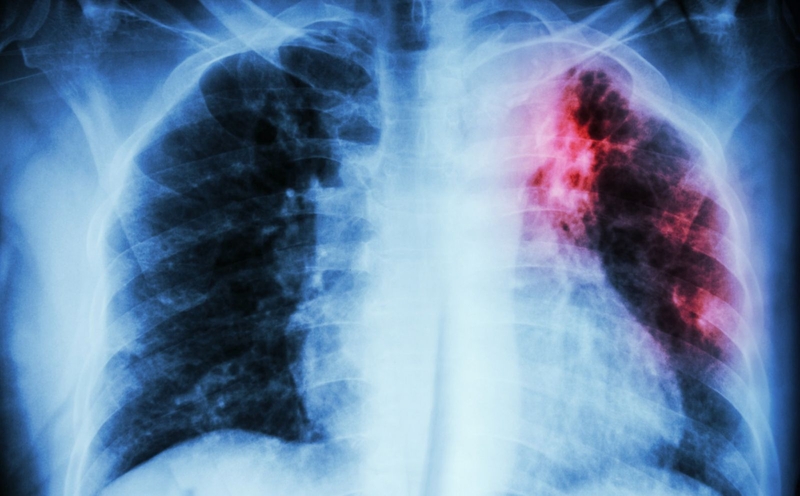

Trong số các loại bệnh lao thì bệnh lao phổi là bệnh khá phổ biến với tỷ lệ mắc bệnh cao. Tuy nhiên, có những thể lao ngoài phổi khác cũng cần xét nghiệm, chẩn đoán để điều trị kịp thời và hiệu quả. Cùng tìm hiểu một số bệnh lao ngoài phổi hay gặp nhất qua bài viết dưới đây nhé!

Bệnh lao phổi là bệnh khá phổ biến với tỷ lệ mắc bệnh cao Bệnh lao phổi là bệnh khá phổ biến với tỷ lệ mắc bệnh cao

Bệnh lao là một bệnh truyền nhiễm do vi khuẩn Mycobacterium tuberculosis gây ra. Bệnh lao có thể ảnh hưởng đến hầu như bất kỳ bộ phận nào của cơ thể, nhưng lao phổi là dạng bệnh phổ biến nhất.